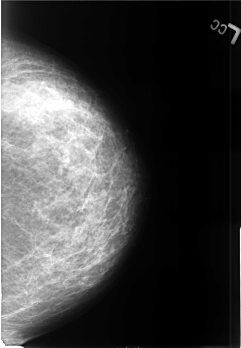

Volume: benign_without_callback_02 Case: B-3446-1

B_3446_1.LEFT_CC

LEFT_CC LINES 4512 PIXELS_PER_LINE 3128 BITS_PER_PIXEL 12 RESOLUTION 50 NON_OVERLAY